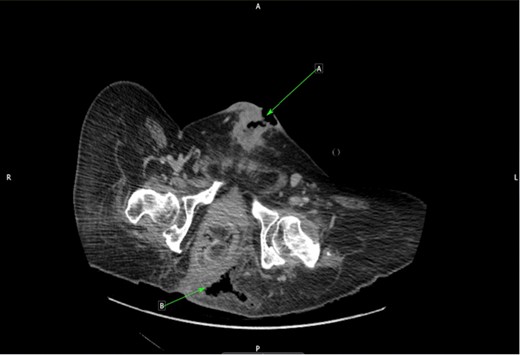

However, as a result of the pain that the patient was experiencing, regular position changes were not maintained, leading to the development of a Grade 4 (full thickness tissue loss with exposed bone) sacral pressure sore. This ultimately resulted in an emergency surgical admission ahead of his planned operation date as he had developed signs of sepsis. On examination, the sacral sore measured 3 cm in depth and 15 cm wide, with visible bone and surrounding cellulitis. Clinically, there were no signs of necrotizing fasciitis. The patient was started on intravenous antibiotics and his pressure sore managed by the tissue viability nursing team. A repeat CT scan was performed and this demonstrated air within the left ischial rectal fossa with evidence of osteomyelitis in the coccygeal bones (Fig. 2). A joint review was undertaken by the colorectal and urology team as an inpatient. Due to the proximity of the anus to the sacral pressure sore and the patient’s chronic problem with constipation (requiring manual evacuation), it was decided after discussion with the patient that an end colostomy should be performed alongside the excision of SCC.

CT cross-sectional plane of pelvis. (a) Infiltrating SCC along suprapubic tract. (b) Air in left ischiorectal space from sacral sore.